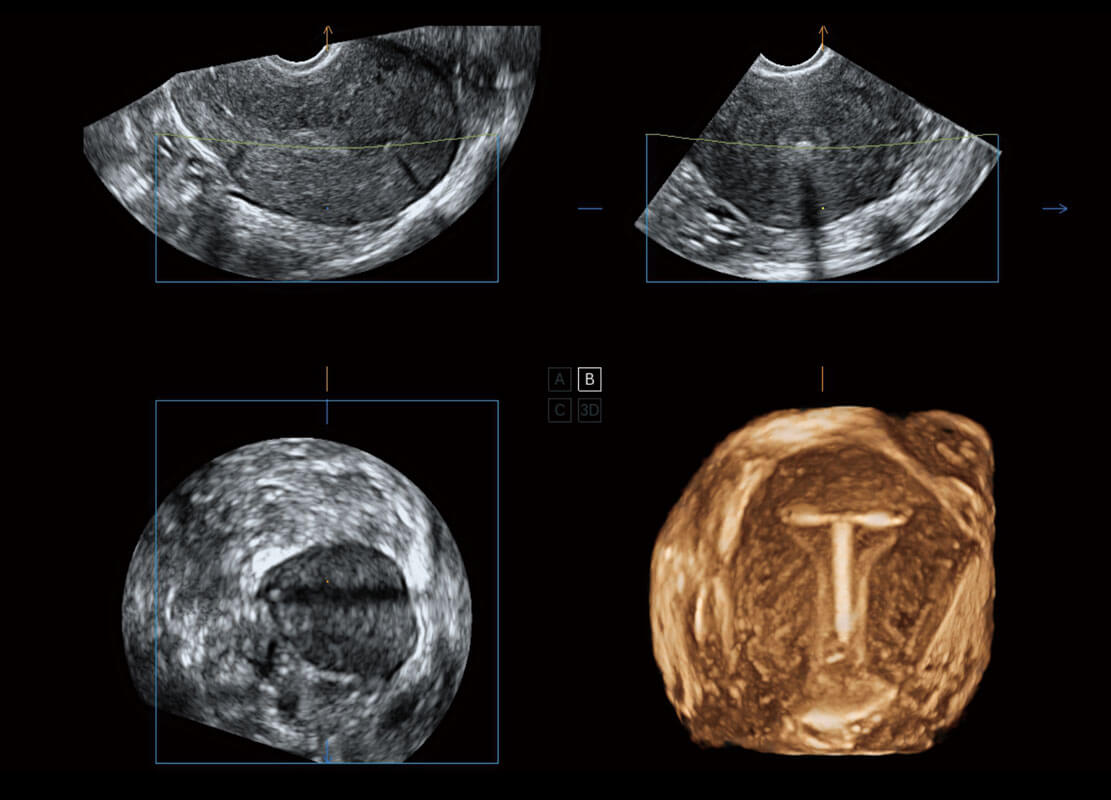

腔内三维-宫内节育器

腔内三维-光影成像

P60搭载一系列胎儿心脏成像技术,实现精细的胎儿心脏评估。

胎心容积成像